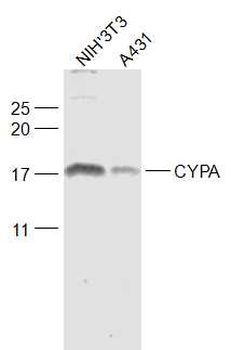

Anti-Cyclophilin A/PPIA Antibody [orb19174]

FC, ICC, IF, IHC, IHC-Fr, WB

Human, Mouse, Rat

Rabbit

Polyclonal

Unconjugated

10 μg, 100 μgCYPA Rabbit Polyclonal Antibody [orb100498]

FC, IF, IHC-Fr, IHC-P, WB

Bovine, Canine, Porcine, Rabbit

Human, Mouse, Rat

Rabbit

Polyclonal

Unconjugated